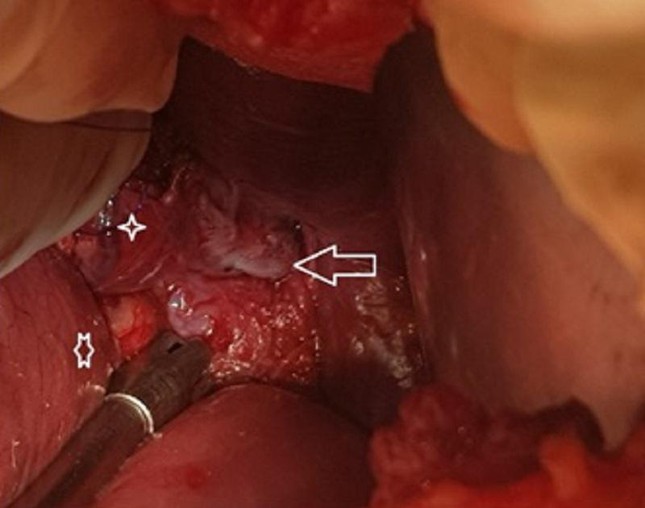

Vị trí thực quản bị vỡ của bệnh nhân được bác sĩ phát hiện trên camera nội soi

Các bác sĩ đã quyết định thực hiện phương pháp nội soi để kiểm tra đường tiêu hóa, dạ dày của người bệnh. Trên camera nội soi ghi nhận một đường rách thực quản dài 3cm ở cạnh trái thực quản. Sau hội chẩn nhanh, bệnh nhân được chỉ định thực hiện cuộc phẫu thuật khâu lại vết rách và xử lý vị trí tổn thương nhằm ngăn chặn tình trạng nhiễm trùng.